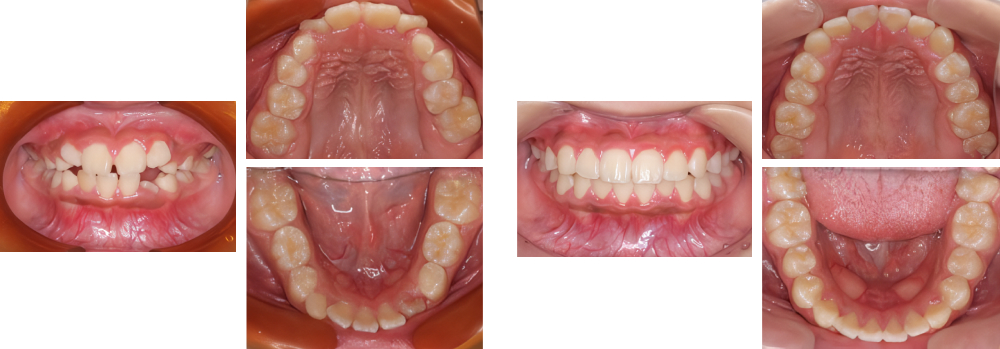

小児矯正

術前

術後

| 治療内容 | 叢生に対して床矯正を使用し治療を行った |

|---|---|

| 治療期間・回数 | 20カ月間・19回(動的治療まで) |

| 費用 ※自由診療となります |

矯正検査①:33,000円 床装置(ネジあり):77,000円 ×2 床装置(ネジなし):55,000円 ×2 |

| リスク・副作用 |

|